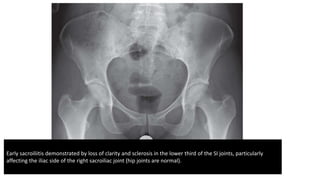

• The cardinal sign – and often the earliest – is erosion and fuzziness of

the sacroiliac joints.

• Later there may be peri-articular sclerosis, especially on the

iliac side of the joint and finally bony ankylosis.

Early sacroiliitis demonstrated by loss of clarity and sclerosis in the lower third of the SI joints, particularly

affecting the iliac side of the right sacroiliac joint (hip joints are normal).

Early sacroiliitis demonstratedby loss of clarity and sclerosis in the lower third of the SI joints, particularly affecting the iliac side of the right sacroiliac joint (hip joints are normal).